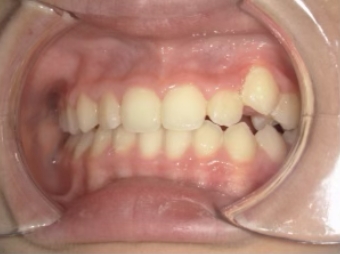

治療中⑨ 中3:14y4m

モノブロック装置で左上八重歯が改善しました

今後、必要によりマルチブラケット法へ移行予定です